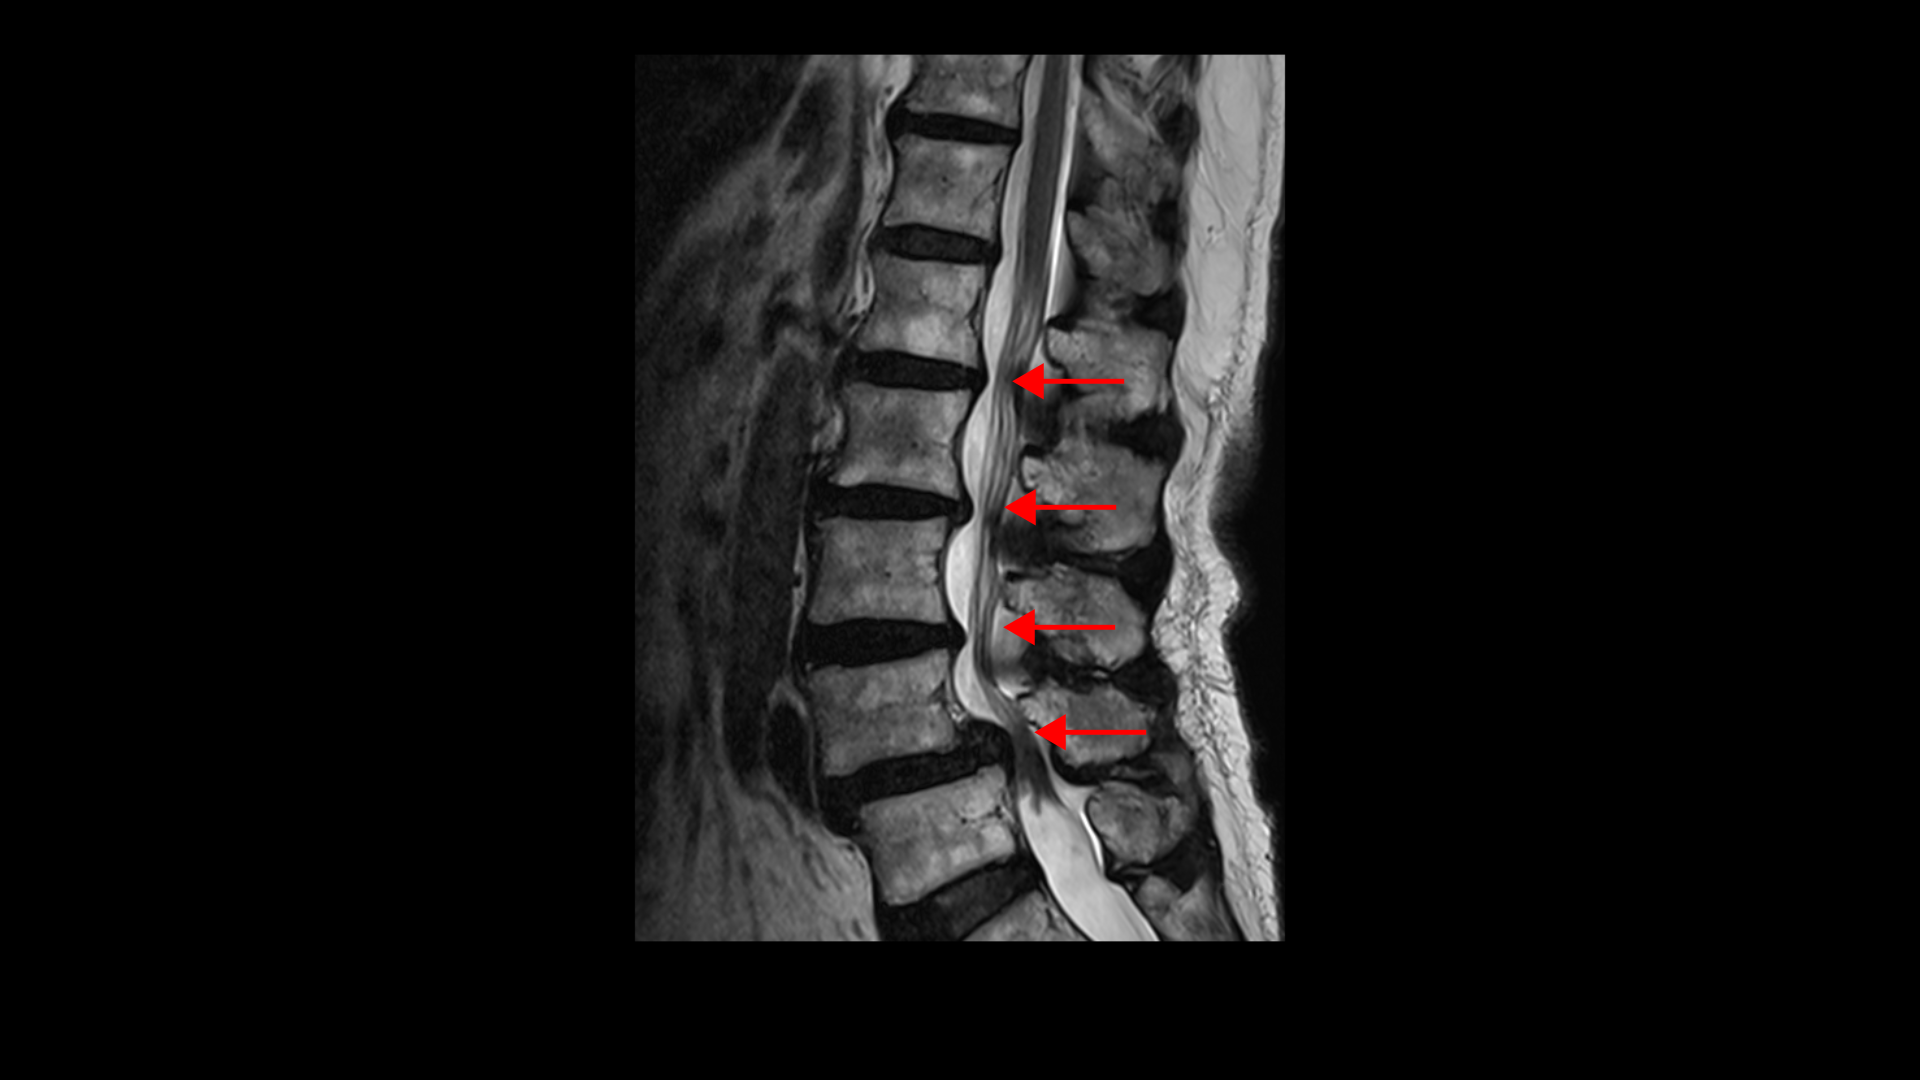

이 환자분 상태를 먼저 설명 드린 후 이분 말씀을 들어보겠습니다. 이분은 협착증을 앓으신 지 약 7년 정도 되셨습니다. MRI를 보면 여러 마디에 퇴행성 디스크가 있고

4번, 5번에는 전방전위증이 있습니다.

전방전위증이 있는 4번, 5번 마디에서는 오른쪽, 왼쪽 신경가지가 나가는 양쪽 추간공이 모두 좁아져 있고

그리고 척추관도 황색인대가 심하게 두꺼워지면서 중심성 협착도 매우 심합니다.

4~5년 전부터 허리와 다리 통증이 심해졌고 걸을 수 있는 거리가 점점 짧아져 올해부터는 100m 정도만 걸으면 쉬어야 되는 상태까지 악화됩니다. 이처럼 협착증은 해가 갈수록 증상이 악화되어 결국은 걸을 수 있는 거리가 점점 짧아져 종국에는 몇 걸음 밖에 못 걷게 되는 것이 특징인데요. 그런데 이렇게 해가 갈수록 협착증 환자의 증상이 나빠지는 걸 MRI에서 신경구멍만 보고 신경이 많이 눌리니까 그런다고만 설명하는 경우가 많습니다. 그러니까 수술해서 신경구멍을 넓혀야 한다는 거죠. 그래서 이 환자분도 신경구멍을 넓히는데 뼈가 밀려 나가 있으니까 나사 박는 유합술을 해야 된다고 대학병원에서 들으셨습니다.

그런데 저희 모커리한방병원은 신경 만이 문제가 아니고 오히려 80세가 넘어갈수록 신경보다 근육 문제가 훨씬 더 중요하다고 말씀 드립니다. 신경구멍이 좁아지는 속도보다 70대 이후 80세가 넘어가면서 근육이 줄어들고 망가지는 속도가 훨씬 더 빠르다고 말이죠. 특히 신경이 자극 받고 눌리는 상태에서는 근육이 위축되고 빠지는 속도가 더 빨라집니다.